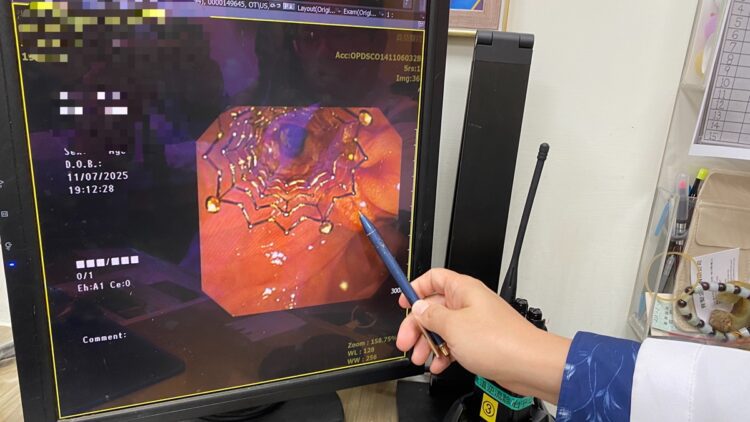

▲手術團隊移除塑膠支架後,以精準技術導管通過狹窄處。(圖/員榮醫院提供)

▲手術團隊移除塑膠支架後,以精準技術導管通過狹窄處。(圖/員榮醫院提供)

經由逆行性胰膽管鏡檢查發現,原有塑膠支架已完全被膽汁阻塞,使肝內膽管擴張。手術團隊以精準技術使導管通過狹窄處先移除塑膠支架後,再置放金屬膽道支架,讓膽汁得以順利排出。術後X光影像顯示,金屬支架位置良好,膽汁引流恢復正常。患者術後症狀明顯改善,包括腹痛、噁心及黃疸皆逐步消退,肝功能指數亦恢復正常。